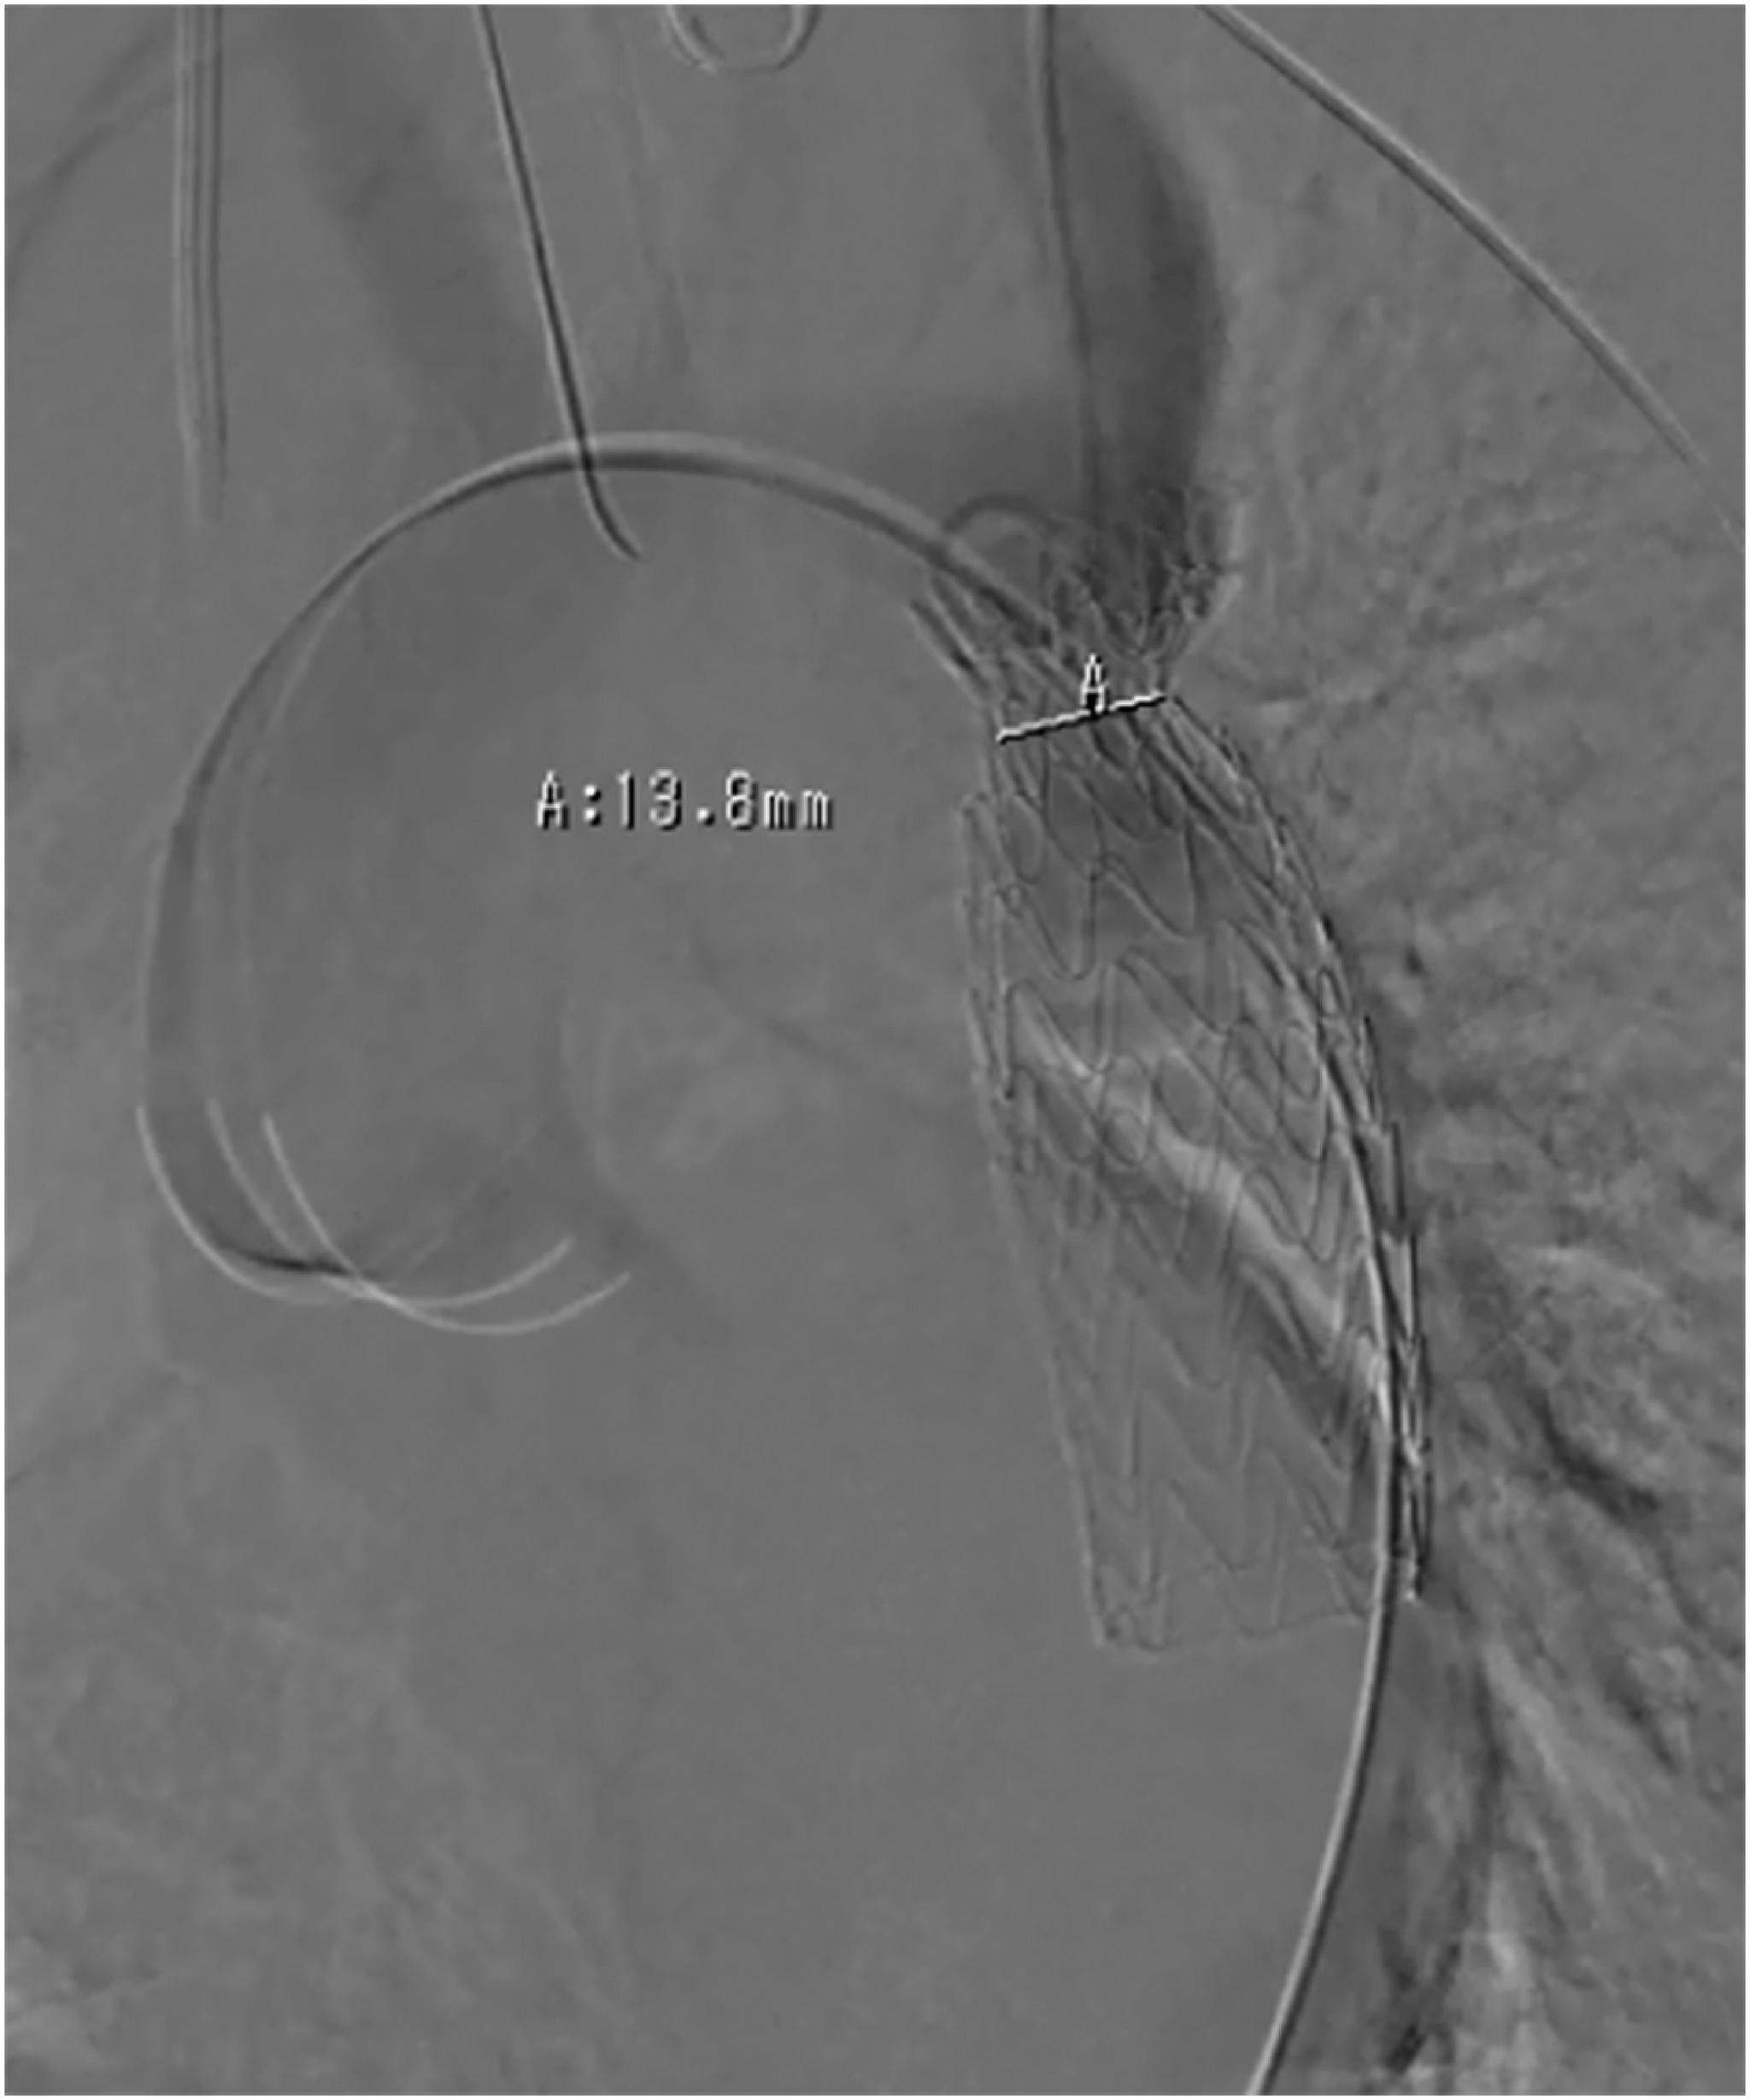

We herein report a case of a 20-year-old man with aortic regurgitation (AR), coarctation of the aorta (CoA), and patent ductus arteriosus (PDA). The preoperative ankle-brachial pressure index was 0.56 in bilateral extremities. Enhanced computed tomography revealed CoA-postductal type. We decided to perform a two-stage surgery: thoracic endovascular aortic repair (TEVAR) for CoA and PDA and then open surgery for AR. TEVAR was successfully performed with deployment of the stent graft at a 31-mm diameter subsequent to balloon dilation. At 8 days after TEVAR, the patient underwent aortic valve replacement via median sternotomy and was discharged without a complication.

我们在此报告一例20岁男性患者,患有主动脉瓣关闭不全(AR)、主动脉缩窄(CoA)和动脉导管未闭(PDA)。术前双侧肢体的踝肱压力指数为0.56。增强计算机断层扫描显示为导管后型CoA。我们决定进行两阶段手术:先对CoA和PDA进行胸主动脉腔内修复术(TEVAR),然后对AR进行开放手术。TEVAR手术成功进行,在球囊扩张后植入了直径为31毫米的覆膜支架。TEVAR术后8天,患者通过正中胸骨切开术进行了主动脉瓣置换,术后无并发症出院。